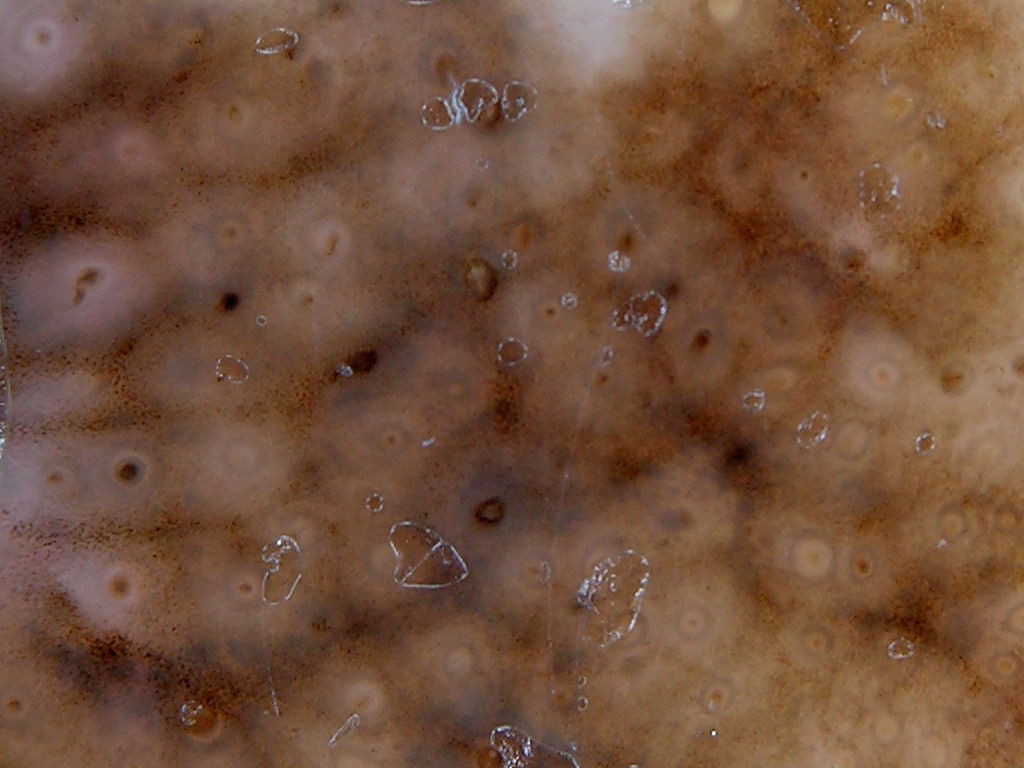

dermatoscopie |

| dermatoscopie |

annulair-granulair |

Dermatoscopische criteria:Bij klassieke dermatoscopische

beoordeling komt een lentigo maligna uit ergens tussen dysplastische naevus

en melanoom. Er zijn 4 kenmerken die horen bij LMM:

- hyperpigmented follicular

openings

- annular granular pattern (ringen of zeshoekige structuren opgebouwd

uit fijne dots), soms peppering (zeer veel dots)

- rhomboidal hyperpigmentation

(verdikking van de gepigmenteerde ringen rond de haarfollikels tot hoekige ruitvormige

pigmentaties)

- obliterated hairfollikels

Daarnaast kunnen grijzige pigmentaties

aanwezig zijn of veel verschillende kleuren.